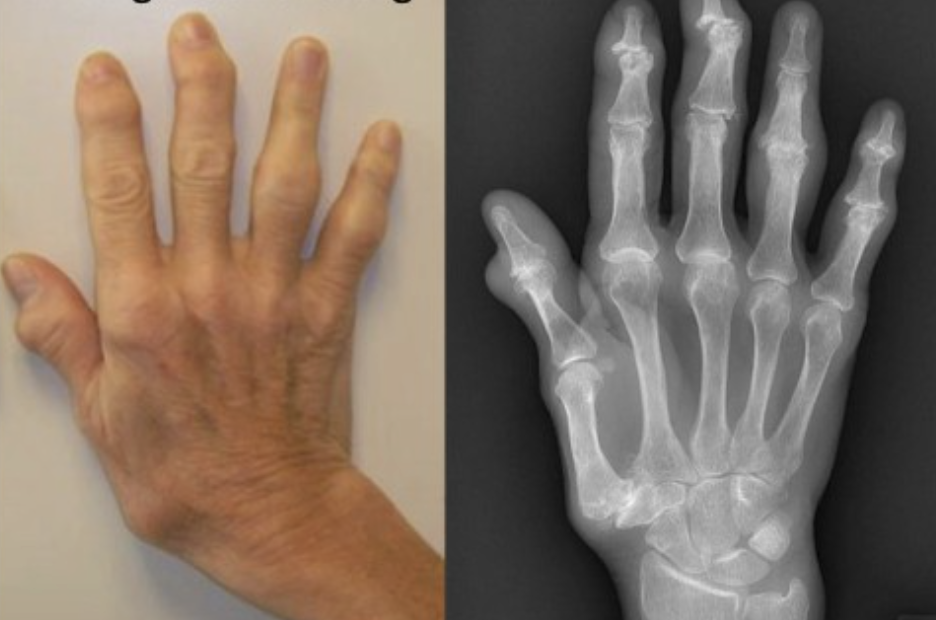

- Glutathione as a mediator of cartilage oxidative stress resistance and resilience during aging and osteoarthritis.Zhu S, Makosa D, Miller B, Griffin TM.Connect Tissue Res. 2020 Jan;61(1):34-47. doi: 10.1080/03008207.2019.1665035. Epub 2019 Sep 15.PMID: 31522568 Free PMC article. Review.